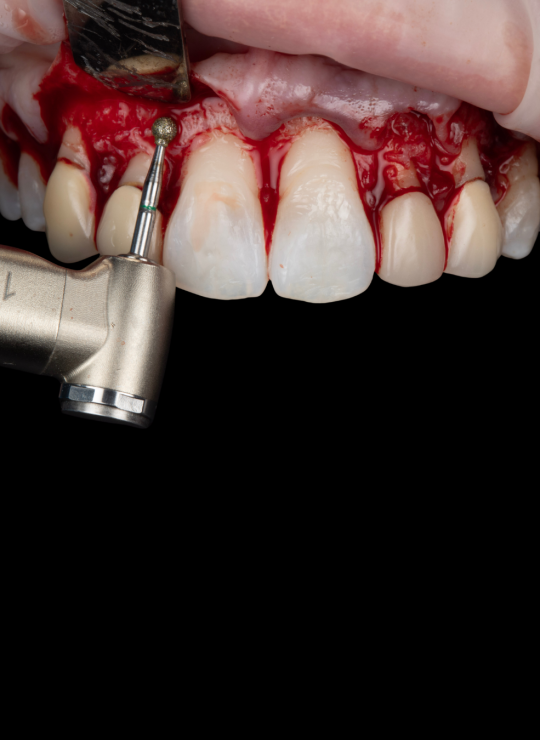

Acquire comprehensive skills in osseous surgery, instrumentation, suturing techniques, and flap reflection for precise and efficient crown lengthening procedures.

Surgical techniques for aesthetic crown lengthening: flap design, bone recontouring, and suturing

Surgical techniques for posterior crown lengthening: flap design modifications, osseous recontouring, suturing